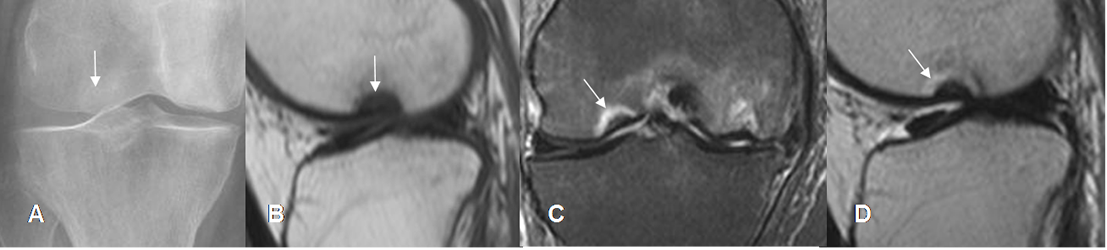

Se ha utilizado la escala de Kellgren-Lawrence (KL) para valorar la osteoartritis, con Rx simple: (42). (Fig 202).

Fig 202. Escala de la osteoartritis.

A: Rx AP. Estado 1: Incipiente formación de osteofito, en el cóndilo femoral medial.

B: Rx AP. Estado 2: Osteofito femoral, con leve disminución del espacio femorotibial.

C: Rx AP. Estado 3: Osteofitos con pérdida del espacio femorotibial.

D: Rx AP. Estado 4: Osteofitos con pérdida del espacio y esclerosis asociada.